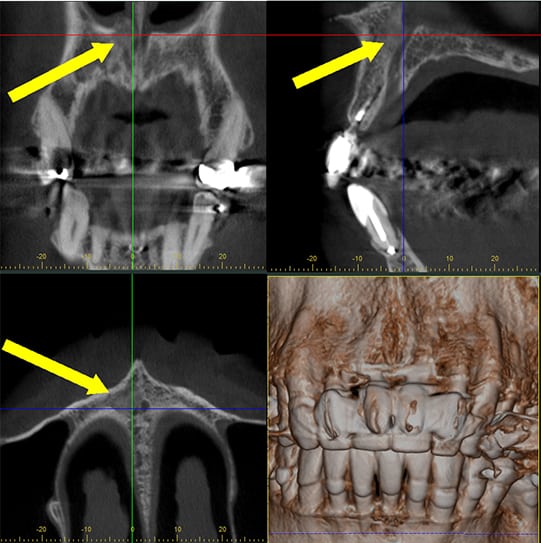

The Panoramic OP 3D LX is an advanced dental imaging system designed to provide a complete, high-resolution view of your entire mouth in a single image. This technology captures your teeth, jawbones, and surrounding structures with remarkable clarity, helping dentists identify issues such as cavities, infections, bone loss, and impacted teeth. Its quick, comfortable process makes it an excellent tool for routine check-ups, pre-treatment evaluations, and surgical planning. The OP 3D LX minimizes patient radiation exposure while maximizing diagnostic accuracy, ensuring a safe and effective experience for every patient.